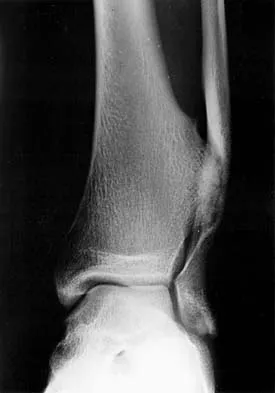

A 58-year-old woman is seen in the emergency department after falling at home. History reveals that she underwent right total knee arthroplasty 2 years ago. Radiographs are shown in Figures 56a and 56b. What is the most appropriate treatment?

The radiographs show an oblique periprosthetic distal femoral fracture. Of the options listed, open reduction and internal fixation is the most appropriate surgical option because a well-fixed, posterior stabilized closed box femoral component is present. Nonsurgical methods are not favored because of the highly displaced, unstable fracture pattern and prolonged immobility. Revision with a stemmed component is an option but would sacrifice more bone stock in this younger patient. Moran MC, Brick GW, Sledge CB, et al: Supracondylar femoral fracture following total knee arthroplasty. Clin Orthop 1996;324:196-209. Raab GE, Davis CM III: Early healing with locked condylar plating of periprosthetic fractures around the knee. J Arthroplasty 2005;20:984-989.